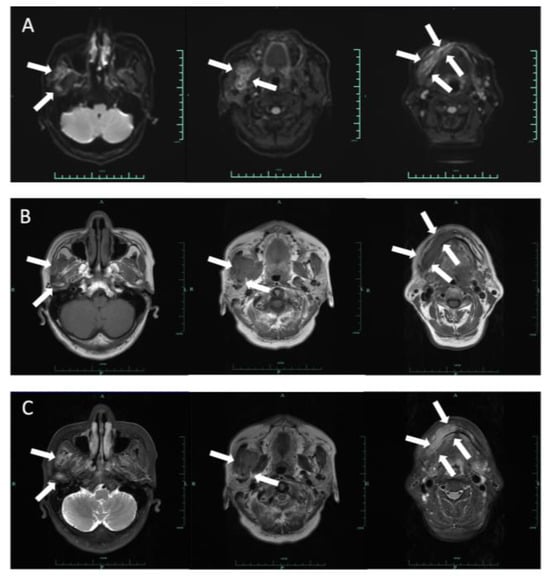

2.1. Case 1